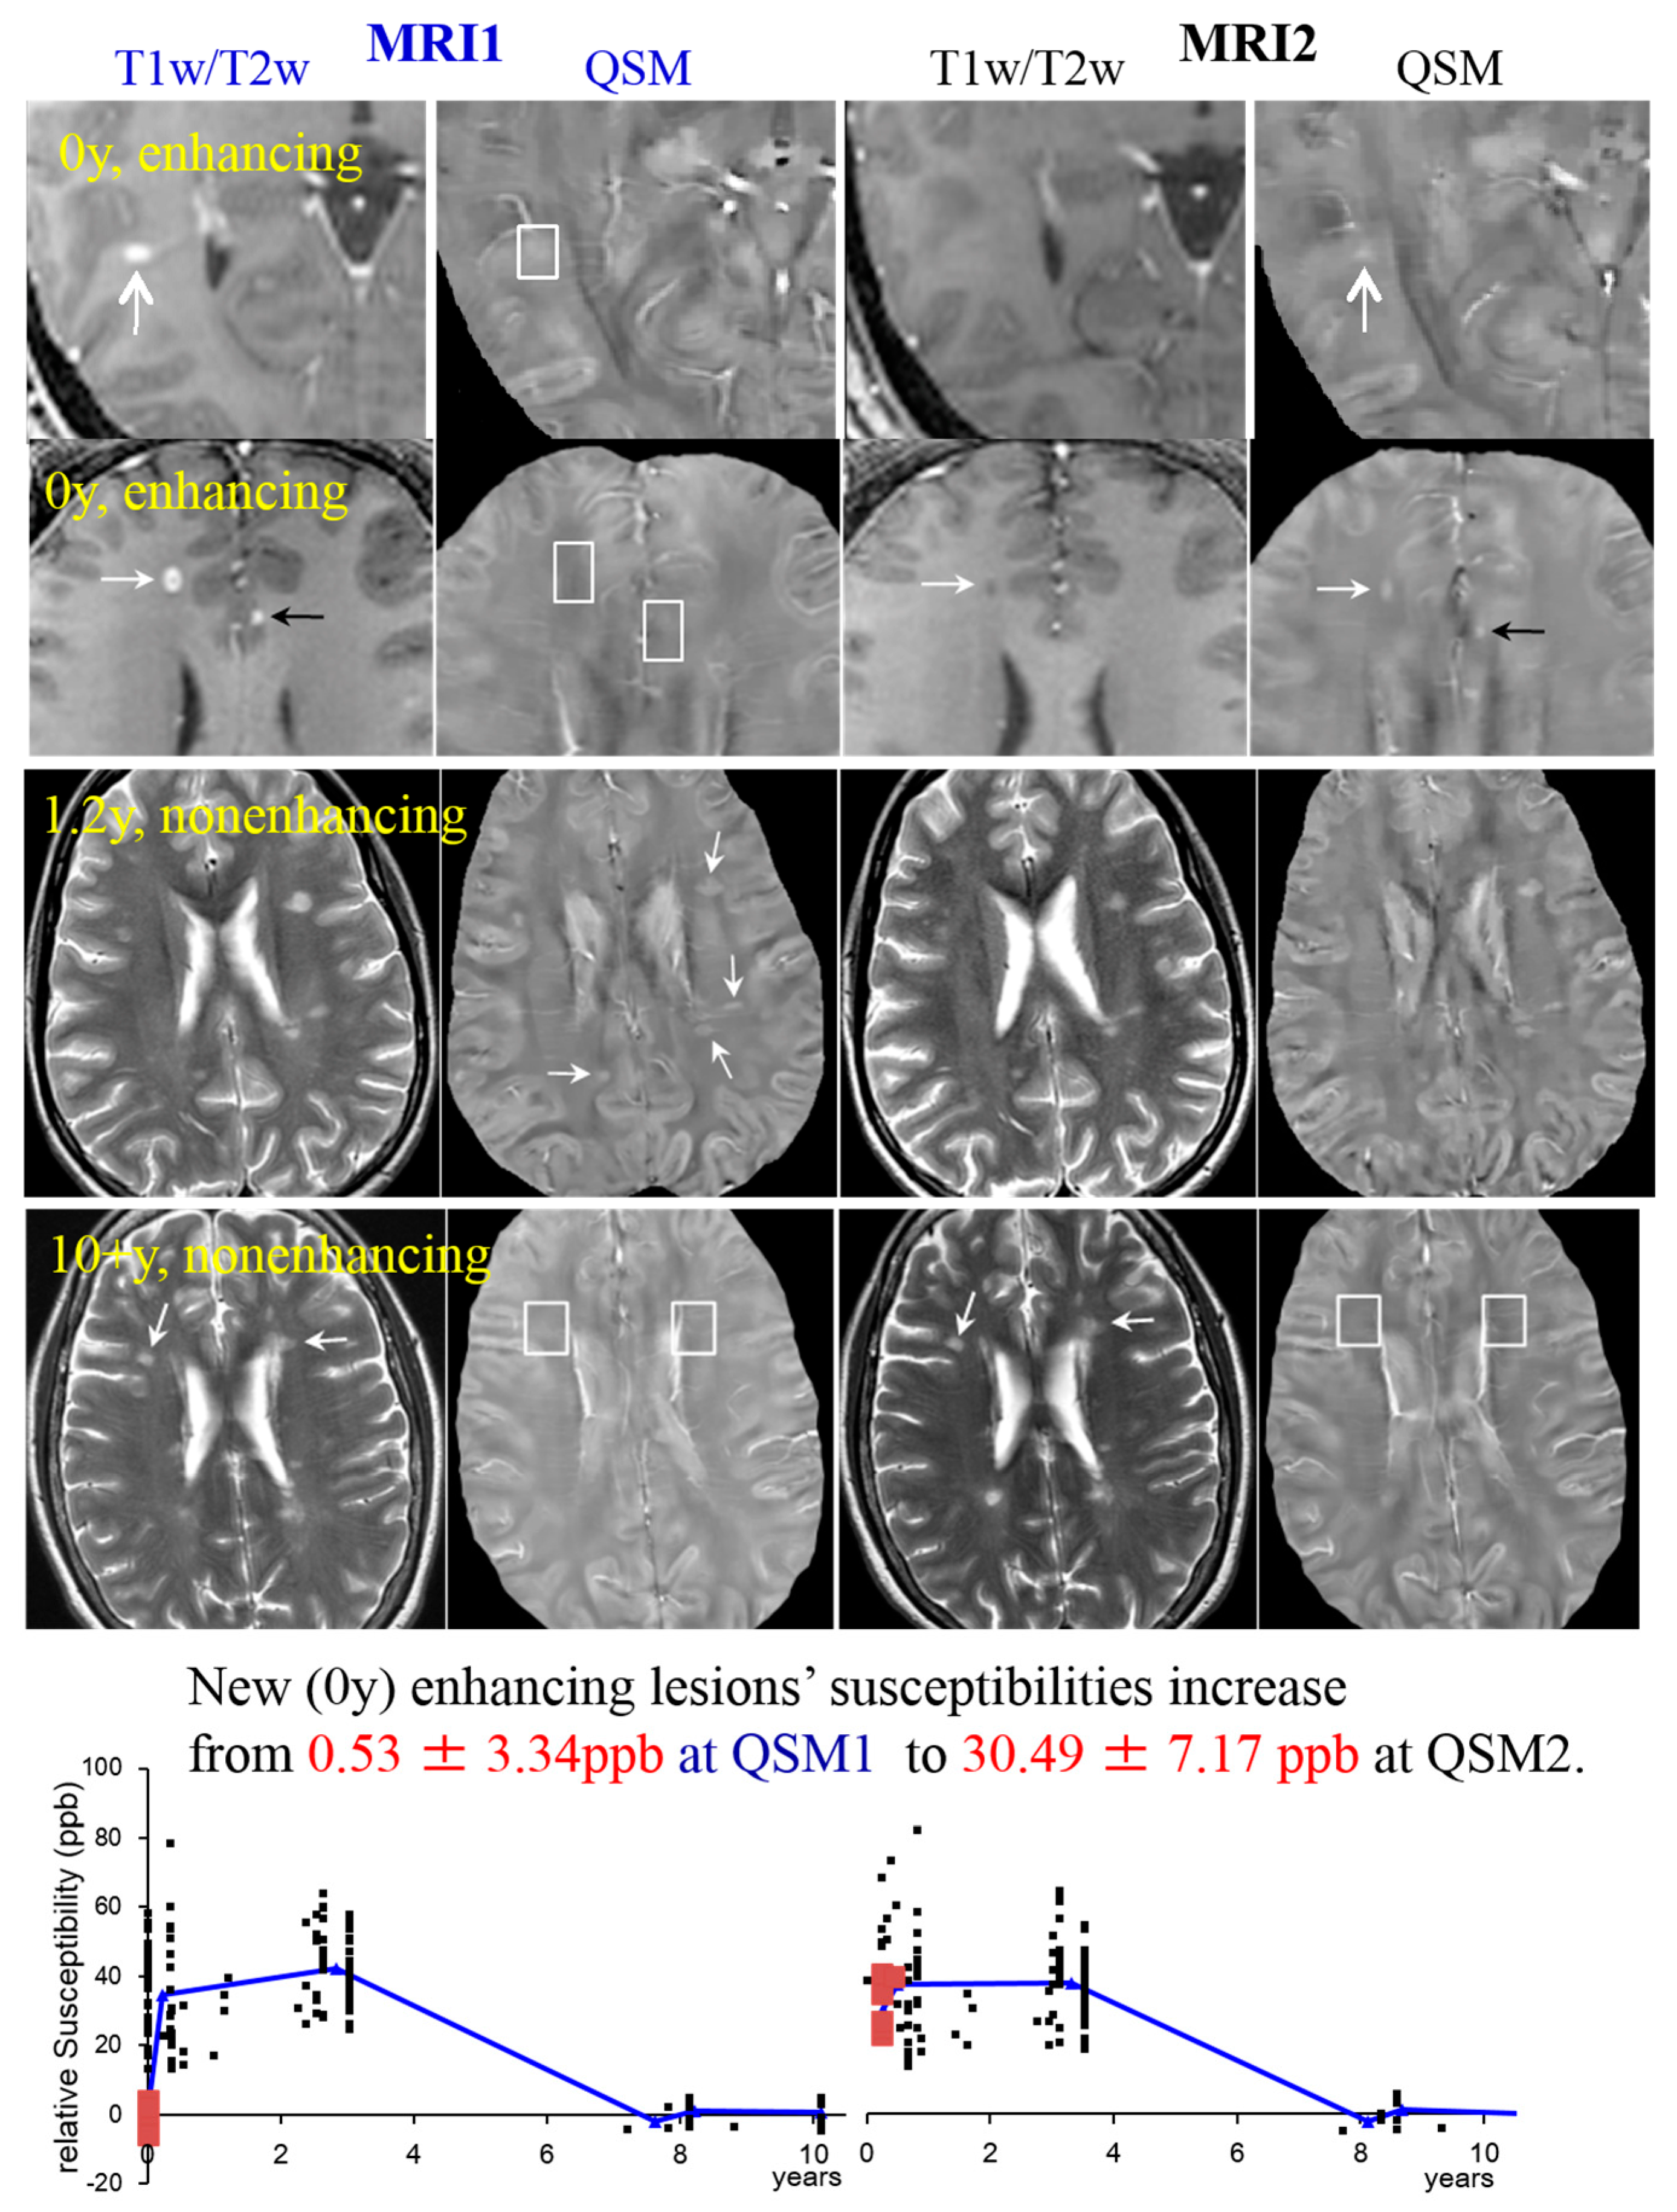

Figure 3. MS lesions on T1w (1st and 2nd row)/T2w (3rd and 4th row) and QSM at MRI1 (left, in blue) and a follow-up study at MRI2 (right, in black). The white boxes indicate the position of lesions identified on T1w, which are invisible on QSM. White arrows point at lesions in general; black arrows point at transient lesions, which disappear (appear T1 isointense) in the follow-up study (MRI2). Lower graphs: 32 cases are shown to exemplify lesions at various ages. The susceptibility of acute lesions (0 y) relative to NAWM jumped from MRI1 to MRI2 (red squares at bottom graph, interval between MR examinations = 0.43 ± 0.16 years). (Source: [42]).Figure 3. MS lesions on T1w (1st and 2nd row)/T2w (3rd and 4th row) and QSM at MRI1 (left, in blue) and a follow-up study at MRI2 (right, in black). The white boxes indicate the position of lesions identified on T1w, which are invisible on QSM. White arrows point at lesions in general; black arrows point at transient lesions, which disappear (appear T1 isointense) in the follow-up study (MRI2). Lower graphs: 32 cases are shown to exemplify lesions at various ages. The susceptibility of acute lesions (0 y) relative to NAWM jumped from MRI1 to MRI2 (red squares at bottom graph, interval between MR examinations = 0.43 ± 0.16 years). (Source: [42]).

Thirty-two clinically confirmed MS patients underwent two MR exams (denoted by MRI1 and MRI2) with 0.43 ± 0.16 year (y) interval on a 3T scanner. MRI included T2w, T1w, T1w+c and QSM (20, 21). Ages of 162 lesions were measured by examining their first appearance on prior MRIs (over past 0.3–10.6 y) in PACS. The susceptibilities relative to NAWM and temporal rates of change in lesion susceptibility relative to CSF were 0.53 ± 3.34 ppb (parts per billion) and 9.29 ± 1.84 ppb/month(m) for new enhancing lesions (age = 0 y), 38.0 ± 13.6 ppb (higher than NAWM, p < 0.01) and 1.3 ± 2.3 ppb/m (not different from zero, p = 0.38) for nonenhancing lesions at age = 0–4 y, and 4.67 ± 3.18 ppb and −0.11 ± 0.55 ppb/m for old nonenhancing lesions (age > 7 y). Examples are presented in Figure 3, showing that lesion susceptibility initially jumped from that of NAWM to high values for 0 y enhancing lesions (top two rows), became stable at high values for the 1.2 y nonenhancing lesions (3rd row), and decayed back to that of NAWM for the 10 + y nonenhancing lesions (4th row). Individual lesion values at MRI1 and MRI2 time points (Figure 3, bottom row), clearly demonstrate the initial jump (red points).